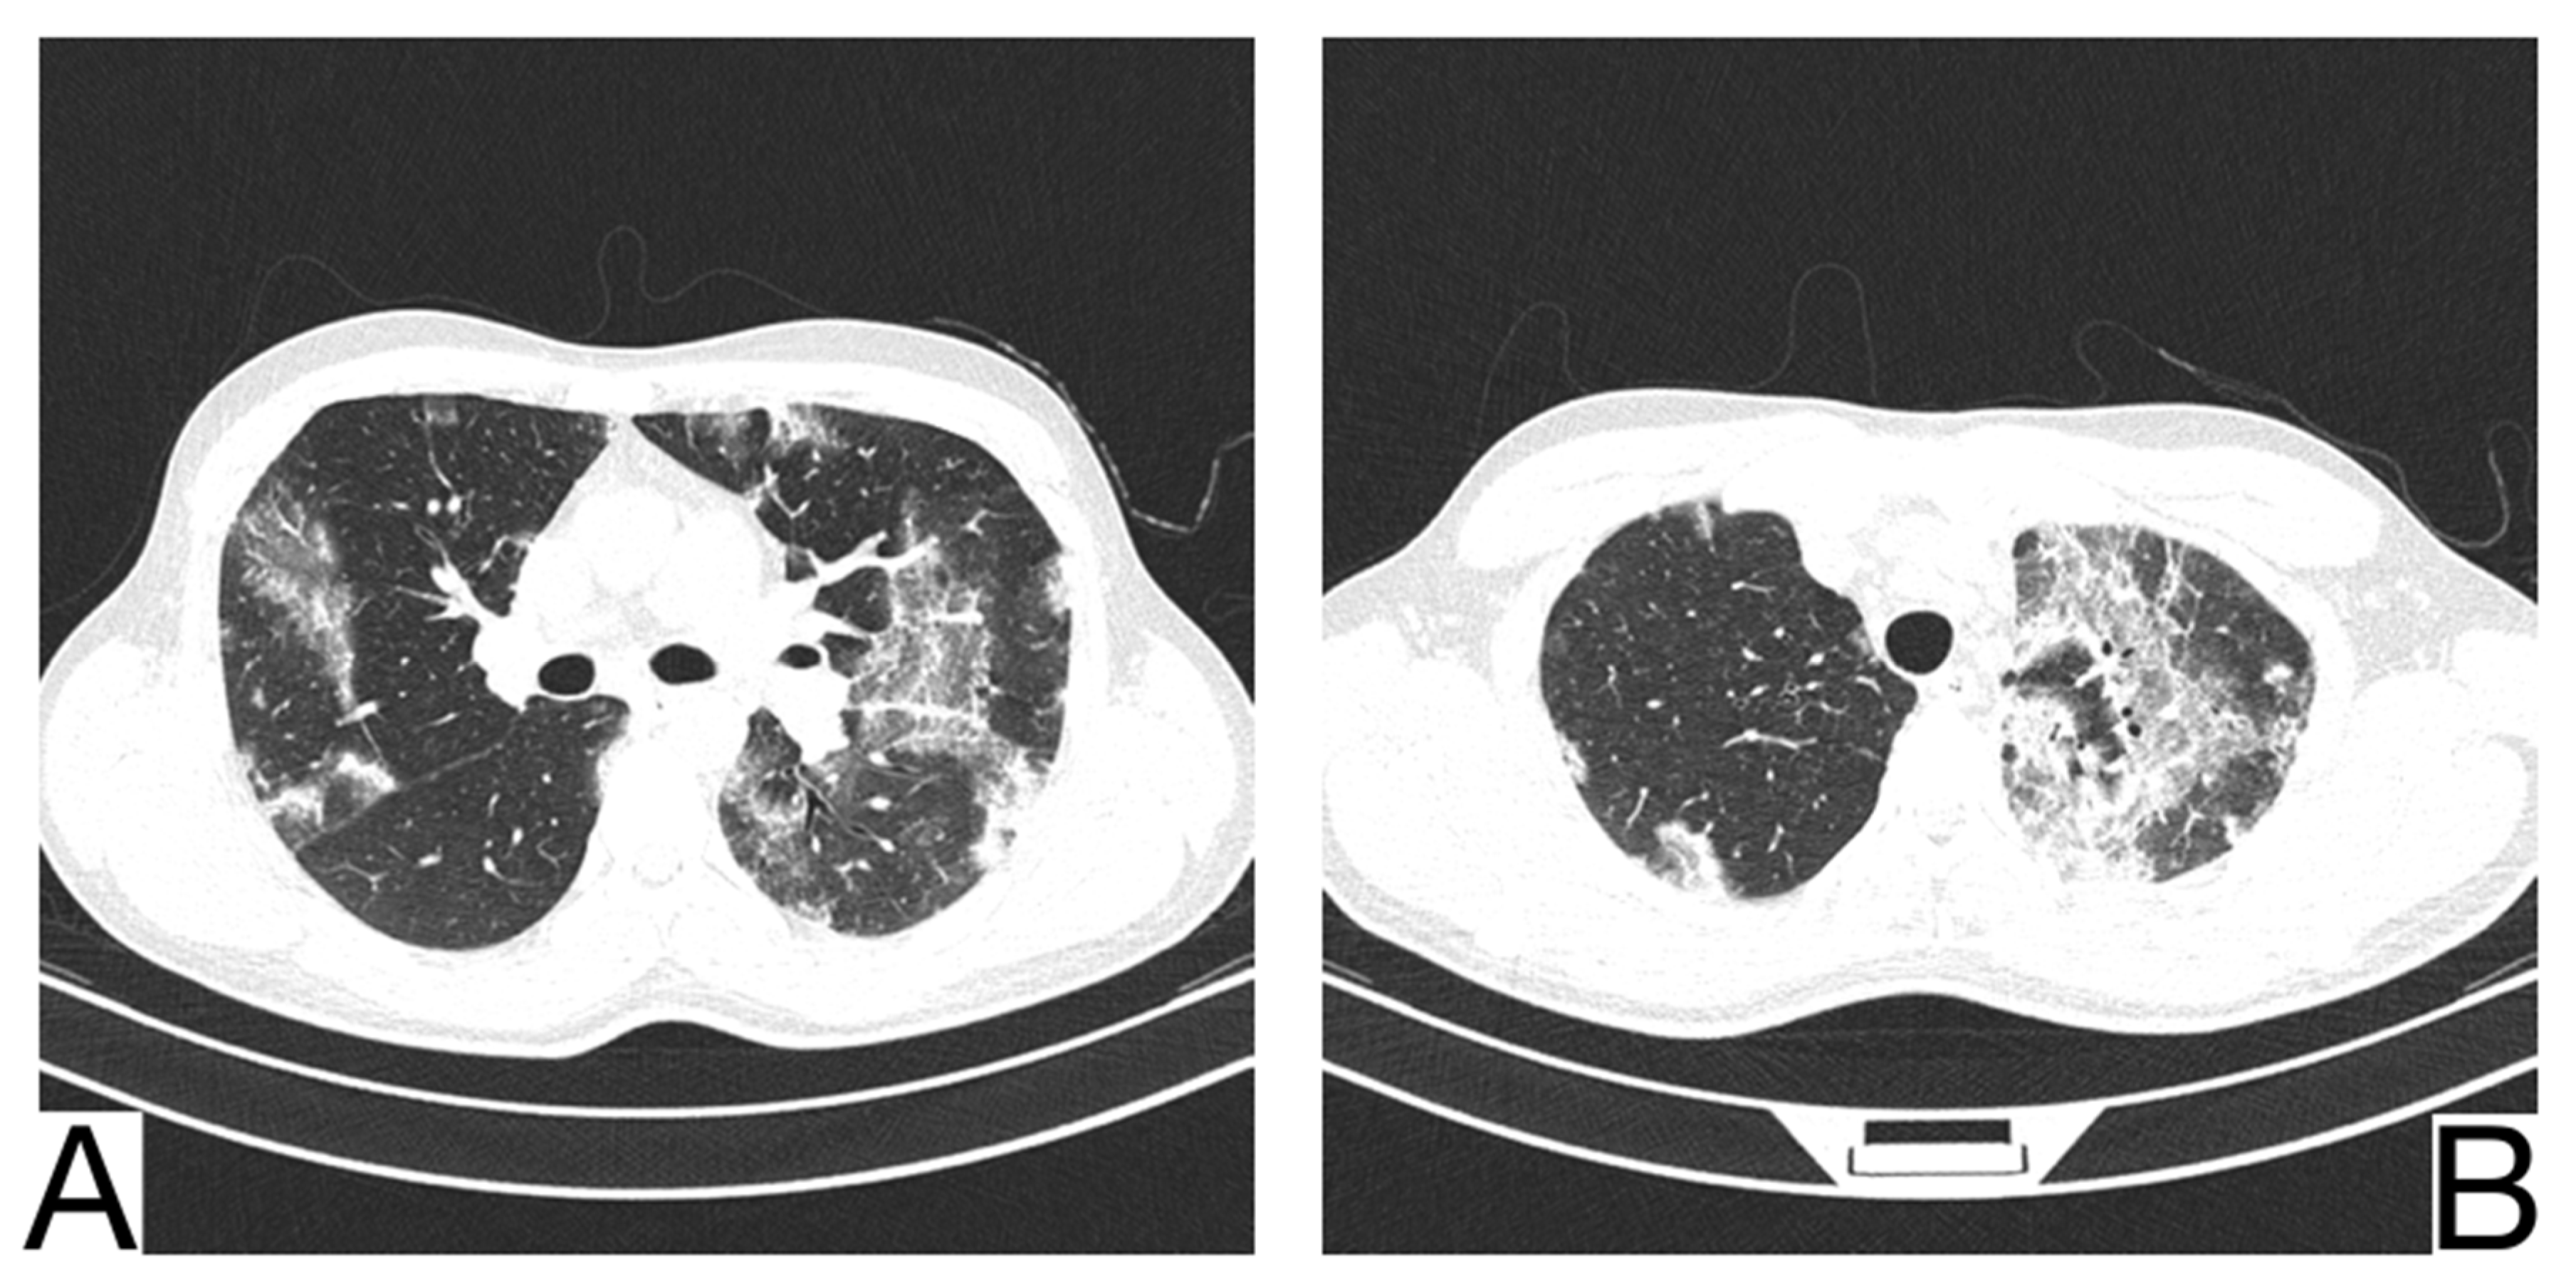

10.12. Differential Diagnosis between COVID-19 Pneumonia and Idiopathic Interstitial Pneumonia (IIP)

COVID-19 pneumonia and IIP represent complex pulmonary pathologies, and the differential diagnosis is frequently challenging.

Idiopathic interstitial types of pneumonia and COVID-19 pneumonia are different entities but share some similar radiological features.

Yet, a discordance between the patients’ anamnesis and the imaging should suggest a possible differential diagnosis [,]. Comparison with previous CT scans is crucial to identify possible chronic or long-standing radiological findings of IIP. In general, the presence of typical and/or additional radiological changes that are less frequent or rare in COVID-19 pneumonia is found in IIP (Figure 13A,B) [,]: the migration of condensation foci (organizing pneumonia); preferential involvement of the lobular periphery, resulting in a “peri-lobular pattern” (pneumonia in organization); ground glass opacities during disease exacerbation; relative reduction of the subpleural lung tissue (nonspecific interstitial pneumonitis, organizing pneumonitis); predominance in the upper fields (bronchiolitis associated with interstitial lung disease, lymphoid interstitial pneumonia, pleuropulmonary fibroelastosis) []; apicobasal gradient and heterogeneous lung involvement (idiopathic pulmonary fibrosis); clear demarcation between the healthy lung parenchyma and the affected parenchyma (idiopathic pulmonary fibrosis) []; the coexistence of other radiological findings such as centrolobular nodules (bronchiolitis associated with interstitial lung disease, organizing pneumonia) and thin-walled cysts (interstitial lymphoid pneumonia) []; the presence of fibrosis that can be appreciated as parenchymal distortion, bronchial traction, and/or honeycombing (idiopathic pulmonary fibrosis, nonspecific interstitial pneumonitis); pleural thickening (pleuropulmonary fibroelastosis); pleural effusions (exudative acute interstitial pneumonia, organizing pneumonia).

Figure 13. Idiopathic interstitial pneumonia (A,B). Bilateral septal thickening and honeycombing with more severe involvement toward the lung bases. Note. Case courtesy of Dr. Hani Makky Al Salam, Radiopaedia.org, rID: 41974.

The differential diagnosis of COVID-19 pneumonia with IIP is challenging because these entities may share common radiological aspects. Therefore, a multidisciplinary approach is crucial to arrive at a final and correct diagnosis [,].